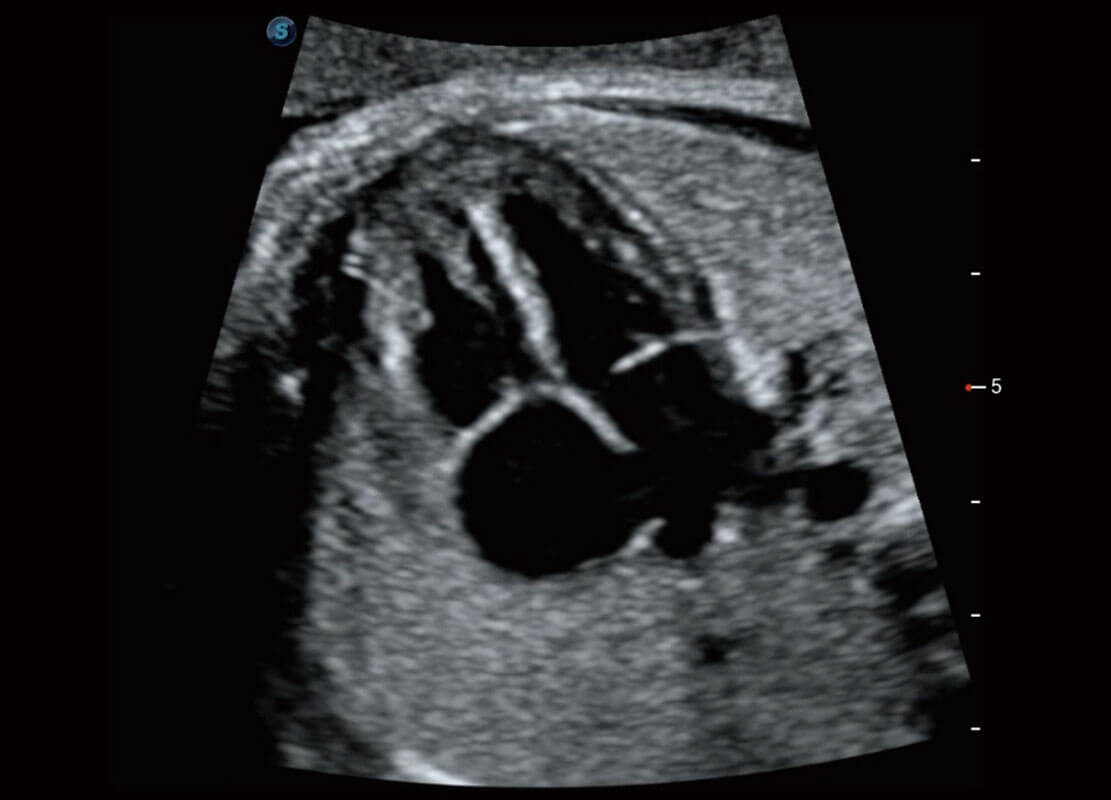

腔内妇科-宫腔分离

腔内妇科-卵巢